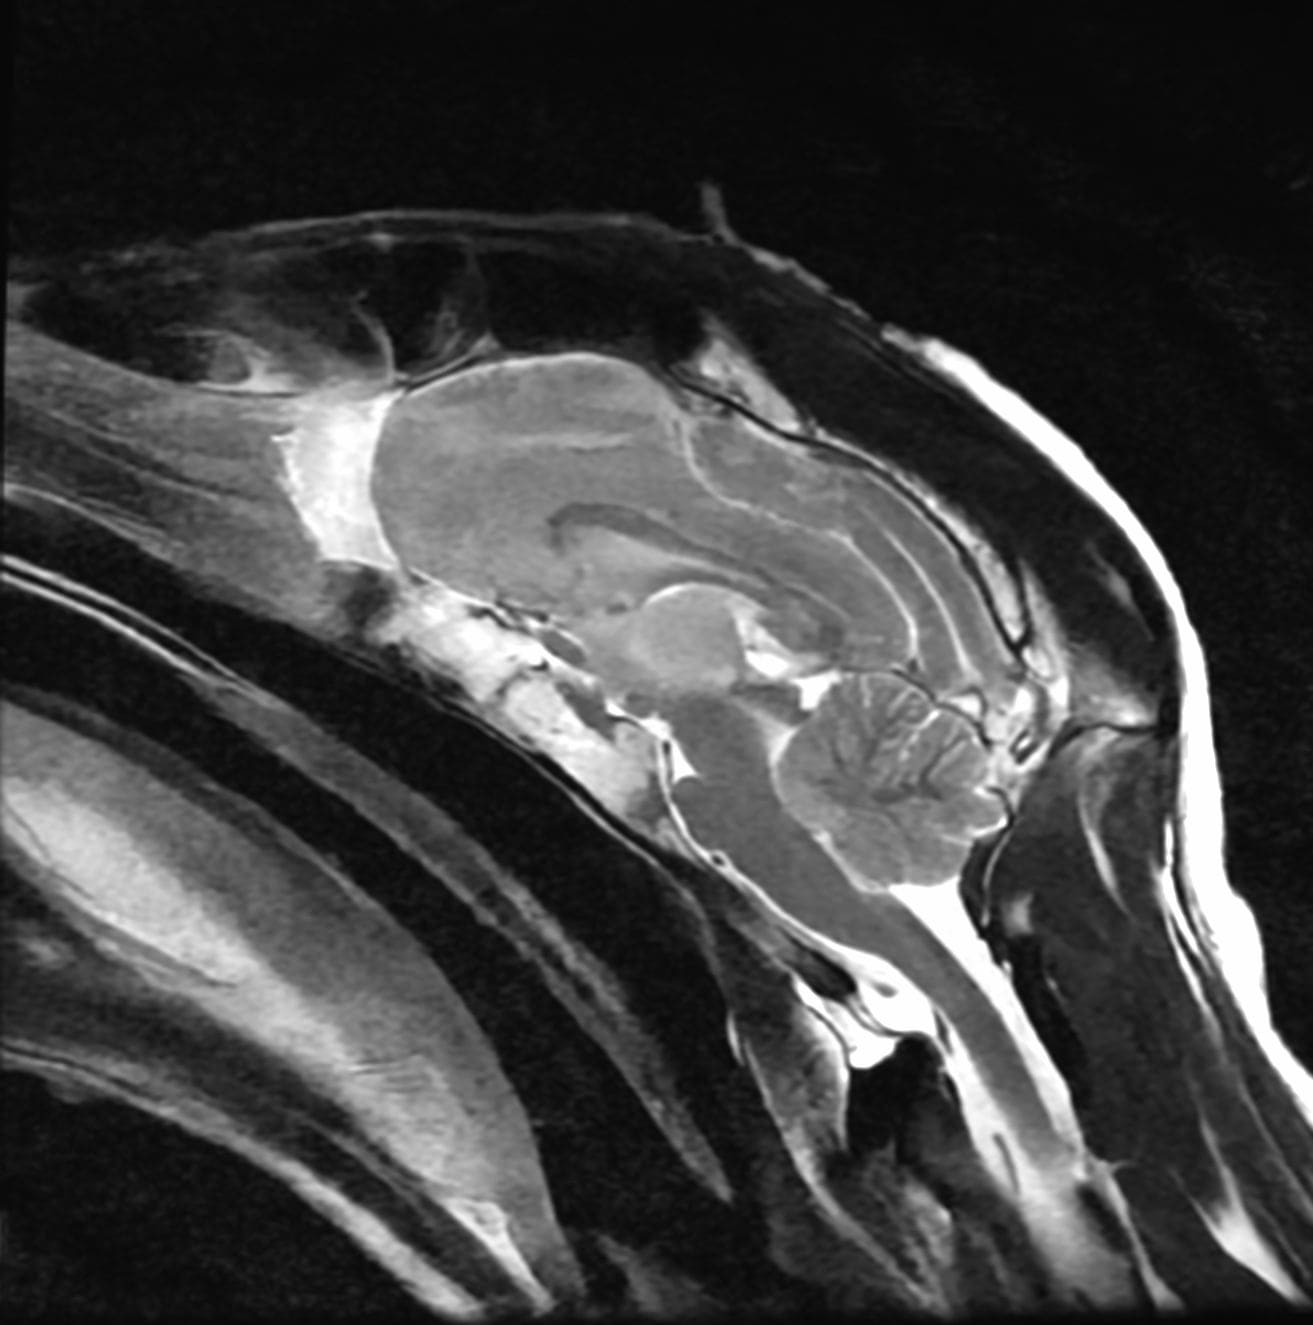

EVAA Radiology provides comprehensive teleradiology services across all subspecialties, with a commitment to excellence and a personal touch—ensuring that referring doctors always have access to a radiologist for discussion whenever needed.

At EVAA Radiology we provide tele-radiology services in the following subspecialties –